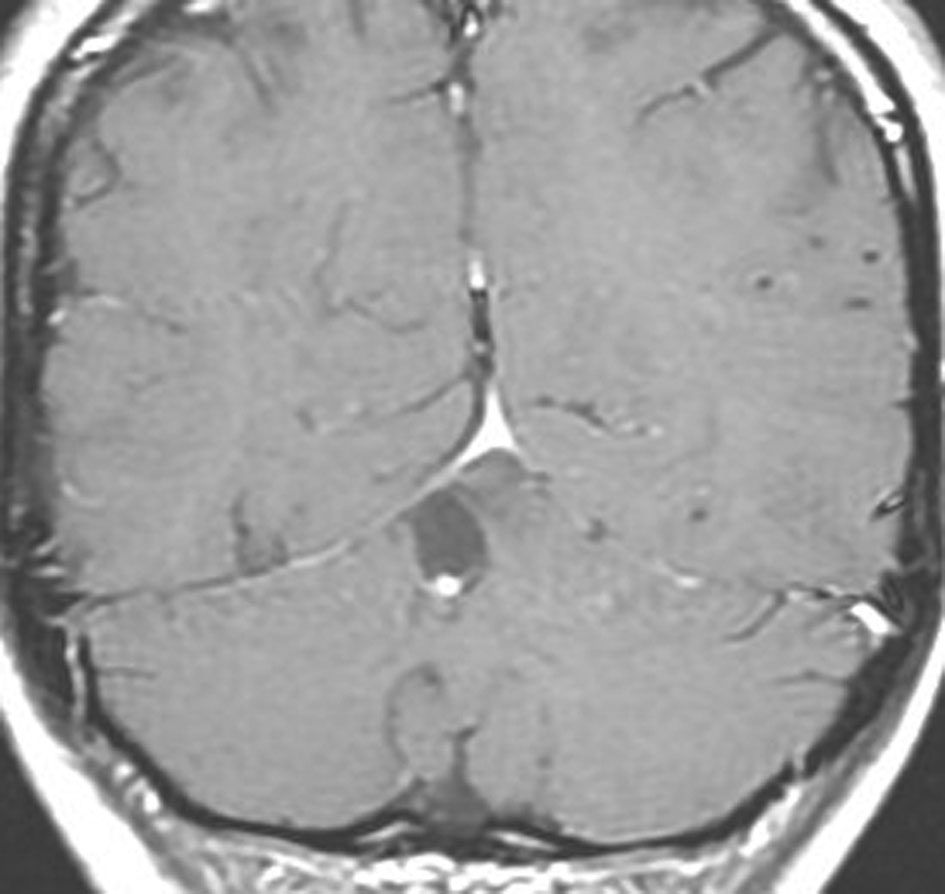

大脳皮質の毛様細胞性星細胞腫

小児期の右大脳頭頂葉にできた毛様細胞性星細胞腫です。小脳と同様に大脳にも壁在結節を作ってのう胞性増大する毛様細胞性星細胞腫というのはよくみかけます。てんかん(けいれん)発作で発症するものが多いです。腫瘍を摘出すると症候性てんかんが止まることが期待できます。治療方法は手術摘出です。腫瘍のある場所が深部で摘出術が神経脱落症状を招くと考えられる場合には,経過観察して,増大するようならガドリニウム増強される腫瘍実質部分にだけ,定位放射線治療することもあります。